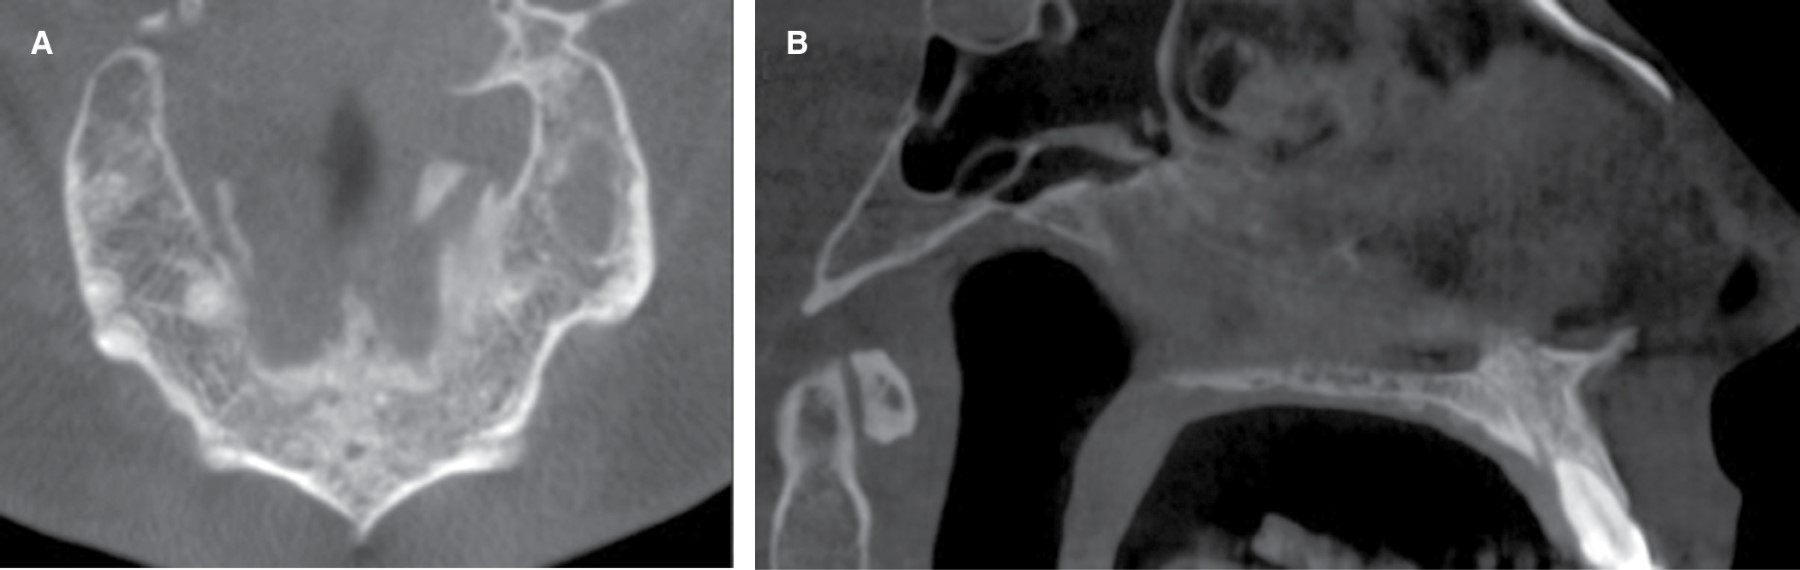

Posterior a consentimiento informado, se realiza biopsia incisional bajo anestesia local, donde se procede a instalar una cánula de descompresión con el objetivo de disminuir el tamaño de la lesión y se indicó aseo con clorhexidina al 0.12% tres veces al día con seguimiento radiográfico a los seis meses (Figura 2A). Con hipótesis diagnóstica de tumor odontogénico adenomatoide, las muestras obtenidas fueron enviadas a estudio histopatológico, el cual mostró una membrana quística con revestimiento epitelial escamoso no queratinizado, de pocas capas, focos de calcificaciones distróficas siendo características sugestivas de quiste dentígero. Tras seis meses de la intervención se realizó una nueva evaluación clínica e imagenológica, donde el paciente relató disminución del tamaño de la lesión y cese de sintomatología opresiva en relación con el sector anatómico comprometido, observándose radiográficamente una disminución del tamaño de la lesión quística en sector anterosuperior con un diámetro de 1.4 × 1.7 × 1.5 cm asociada a la presencia de cánula de descompresión en su espesor (Figura 2B-D).

Se procedió a realizar una nueva intervención quirúrgica bajo anestesia local, donde se efectuó la enucleación y remoción quística con curetaje óseo con exodoncia de supernumerario. Finalmente se realiza relleno de cavidad con hueso microparticulado liofilizado xenogénico (Alpha Bio's GRAFT) más una membrana de colágeno reabsorbible (MEDPRIN ReDuraTM), suturando finalmente la mucosa comprometida (Figura 3A y B). La muestra obtenida (Figura 3C) fue enviada nuevamente a análisis histopatológico evidenciándose metaplasia de epitelio quístico escamoso no queratinizado, rodeado por una cápsula de tejido conjuntivo laxo con infiltrado inflamatorio crónico confirmando diagnóstico de quiste dentígero (Figura 3D). No se observaron recidivas tras seis meses de seguimiento de la lesión (Figura 4).